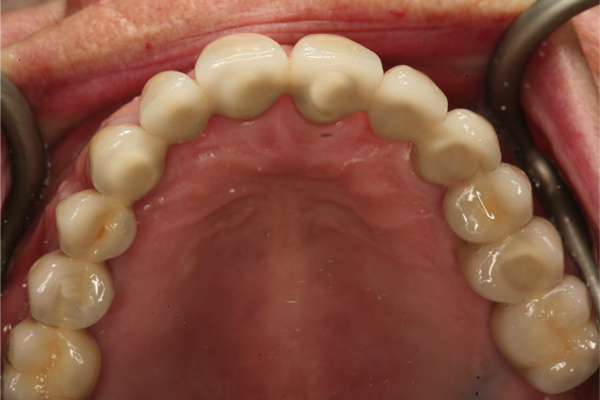

Fig 12. Frontal view (Fig 12) and occlusal view (Fig 13) of clinical application of dual-axis principles. (Images courtesy of Costa Nicolopoulos, BDS)

Figure 12

Fig 13. Frontal view (Fig 12) and occlusal view (Fig 13) of clinical application of dual-axis principles. (Images courtesy of Costa Nicolopoulos, BDS)